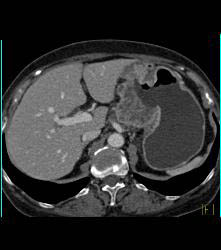

Antral Carcinoma With Adenopathy